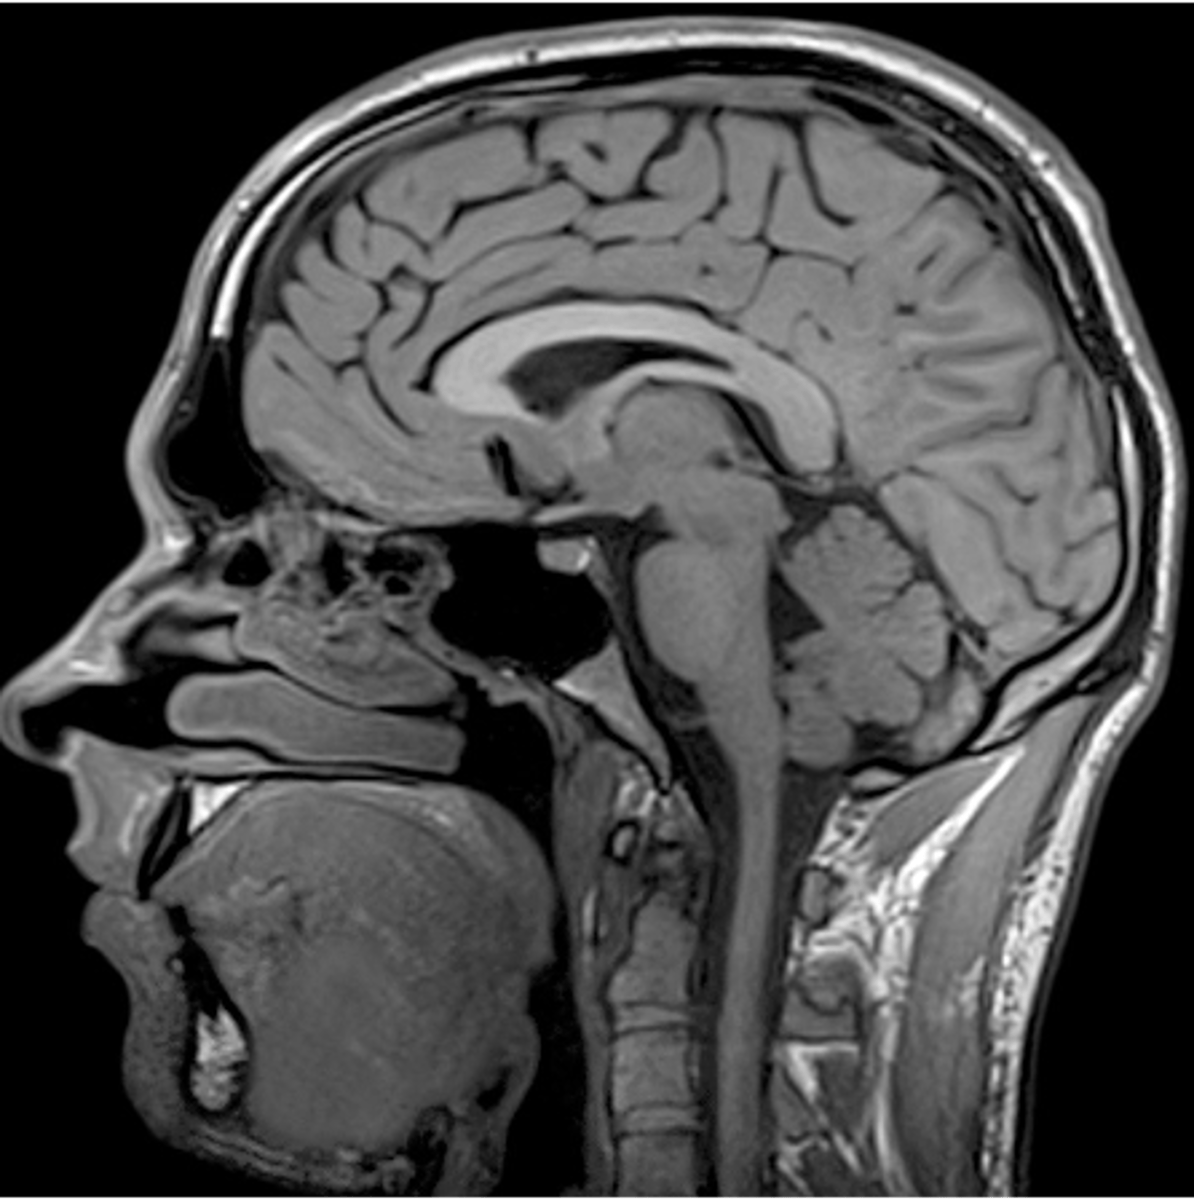

MRI head is most helpful in evaluating __________

soft tissue disturbances (tumors, brain infections, dementia, inflammation)

Before having an MRI, you must make sure the patient doesn't have

metal in the body